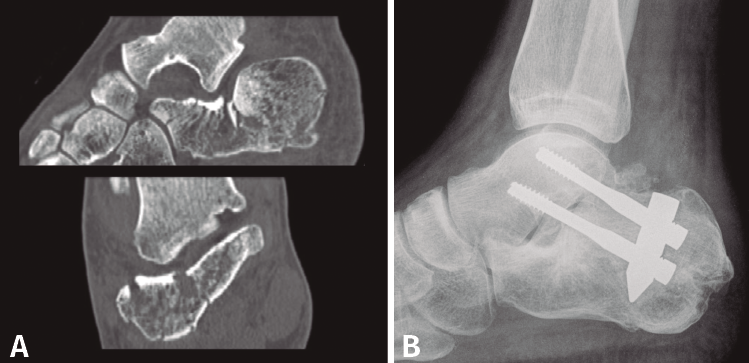

Tras estudiar la posible correlación entre diferentes variables, encontramos que de los 25 pacientes tratados de forma conservadora el resultado fue excelente-bueno en el 68% de los casos, mientras que de los 22 tratados con placa de reconstrucción el 95,4% obtuvieron resultados clínicos valorados como excelentes-buenos. La mitad de los tratados con tornillos canulados percutáneos presentaron resultados favorables y en el caso del sistema Vira® el 80% tuvo resultados excelentes-buenos. En la Figura 3 se muestra un caso tratado quirúrgicamente con este sistema.

Figura 3. Caso tratado con artrodesis primaria. A: tomografía de fractura de calcáneo de tipo III AB; B: resultado posquirúrgico mediante artrodesis primaria con clavo Vira®.